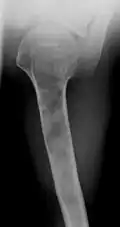

-

X-ray showing enchondromas localized in the humerus of a 37-year-old patient affected with Ollier disease -